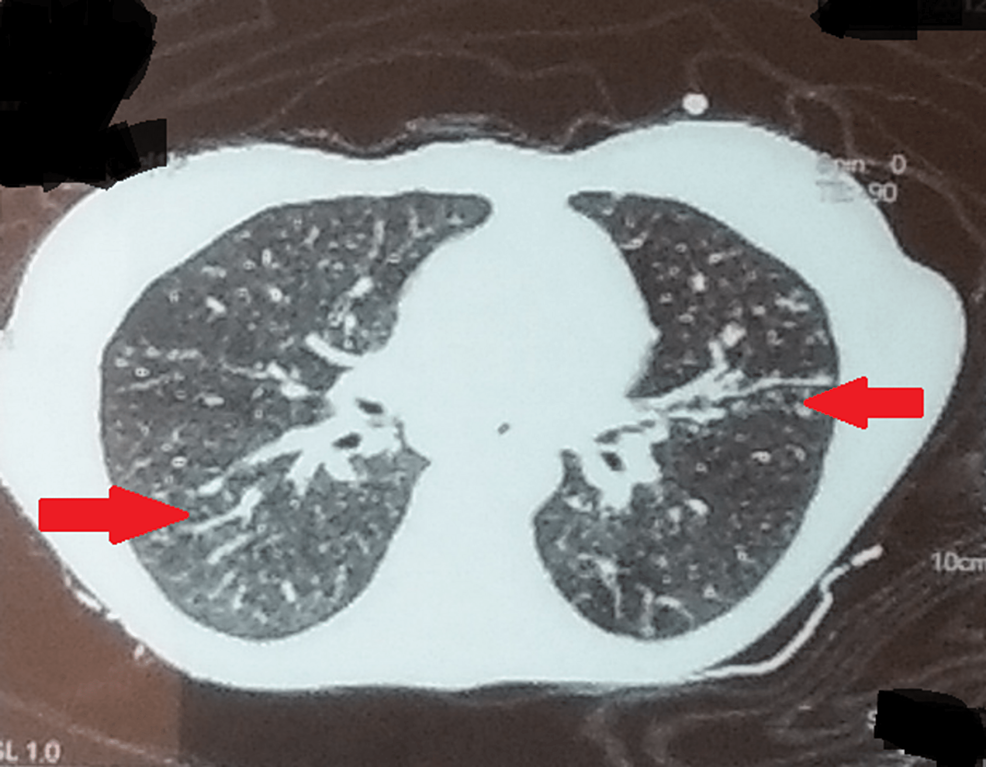

Clinical Overview of Tuberculosis Disease | Tuberculosis (TB。About Tuberculosis | Tuberculosis (TB) | CDC。Tuberculosis | Condition | UT Southwestern Medical Center。William N. Rom 他1名1996年発行大型洋書1001pThis comprehensive clinical reference is edited by experts from the NYU-Bellevue Chest Service, which through its influence in tuberculosis care and education has been an integral part of the formation of the entire specialty of pulmonary medicine. The book draws on this extensive experience to present an authoritative account of the history, epidemiology, microbiology, immunology, clinical treatment, pharmacology, and prevention or control of tuberculosis. The book will serve as a definitive reference for specialists in pulmonary medicine, infectious disease, and public health. 裁断面にやや汚れあります。ご購入の際、念の為、一度在庫確認させて頂きたく存じます。。Multidrug-resistant tuberculosis - Wikipedia。11p程にハイライトされた箇所ありますが、本文には書き込みも傷も汚れもなく、良好な状態です。イヤーノート 2020。南山堂医学大辞典。どうぞ宜しくお願い致します。言語聴覚士国家試験過去問題3年間の解答と解説 2016年版